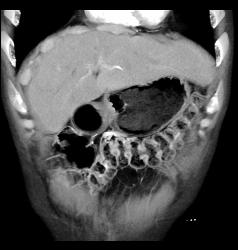

Diagnosis

Hamartoma